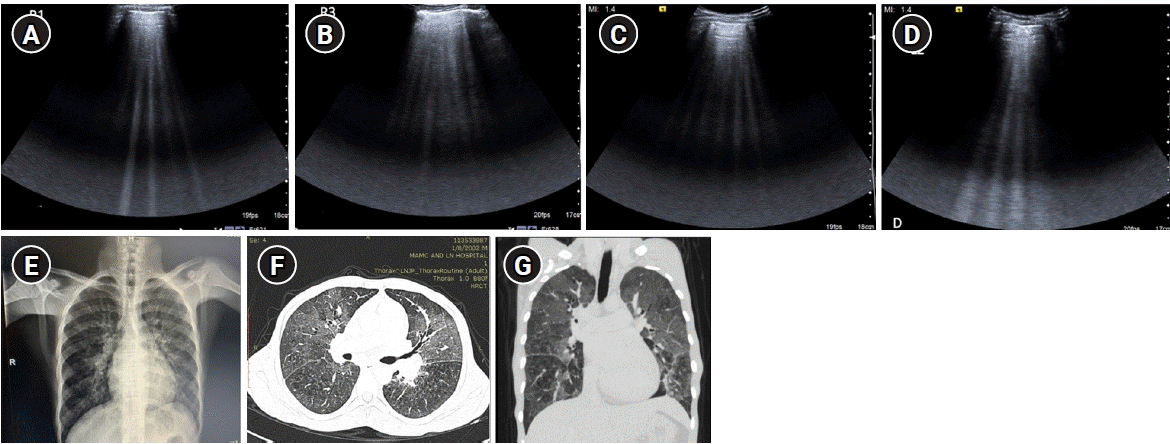

Figure 9.

B-profile. Diffuse interstitial syndrome on ultrasound, diagnosed by the presence of multiple (≥3) B-lines in >1 scanning zone in anterolateral chest wall on each side in a patient presenting with acute dyspnea and hemoptysis. (A, B) Four B-lines are known as “septal rocket” pattern and represent interlobular septal thickening. (C, D) Five or more B-lines are called “ground glass rocket” patterns, representing ground-glass areas on the computed tomography of the chest. the pleural line in this case was regular in appearance. The patient was diagnosed with pulmonary edema based on ultrasound findings. (E) Chest X-ray revealed concordant findings in the form of cephalization of the pulmonary vasculature and prominent interstitial markings. Axial (F) and coronal (G) sections from contrast-enhanced chest computed tomography scan performed in the patient revealed ground glass opacities and Interlobular septal thickening as demonstrated by the “ground glass rocket” pattern and “septal rocket” pattern respectively on ultrasound, providing further confirmation of the diagnosis.